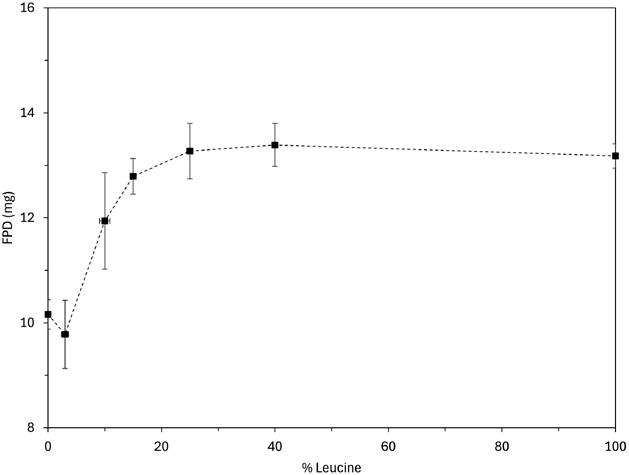

Studies have shown that the optimisation of the excipient, the inactive vehicle of the LNP with the dry powder formulation, can significantly improve formulation characteristics. The combination of both mannitol and leucine has been found to create much smoother and spherical LNPs when observed through a scanning electron microscope, and the addition of ethanol in the inlet feed aided in reducing the particle size of the dry powder product.11